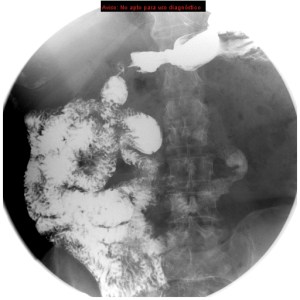

Se solicita tránsito intestinal baritado por proceso actual de vómitos, estreñimiento, historia de sangrado digestivo bajo y anemia sin hallazgos de malignidad tras la realización de colonoscopia y TAC.

Inestino delgado localizado en toda su integridad en hemiabdomen derecho. El ángulo de Treitz (unión entre duodeno y yeyuno) que es la estructura más fija del sistema digestivo, no se encuentra en su localización habitual, lo cual es un hallazgo diagnóstico muy importante.

Se revisarón estudio previos, en un enema baritado y TC se observó:

Enema baritado con ciego (con apéndice visible) en posición anómala, localizado en hipocondrio izquierdo. TAC de adomen con signo de remolino o Twister de vasos. Otro hallazgo sería encontrar la VMS a la izquierda de la AMS.

Diagnóstico: MALROTACIÓN INTESTINAL.